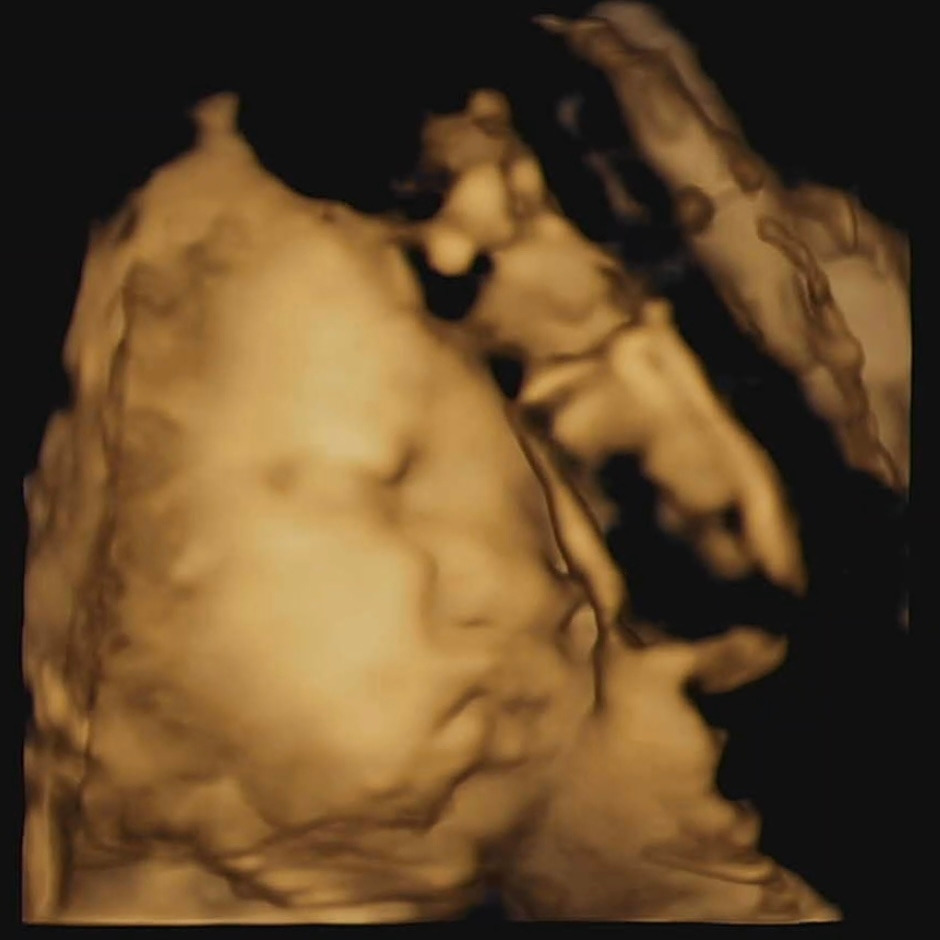

차차의 신체 발달을 간략하게 다시 체크하고 드디어 얼굴로 향한 순간, 얼핏 보이는 완연한 사람의 얼굴에 심장이 철렁했다. 정말 내 안에 사람이 크고 있었다. 차차는 자고 있었는데, 세수하듯 얼굴 위에 양손을 얹고 한쪽 볼에 탯줄을 베고 있었다. 초음파 선생님께서 내 배를 흔들고, 쿡쿡 찌르고, 나보고 크게 웃어보라고 하셔서 차차를 깨우기 위해 열심히 웃어 보였으나 차차는 손 한쪽만 내리고 얼굴을 잘 보여주지 않았다. 그런데 보인 얼굴이, 세상 뾰루퉁한 얼굴로 입술을 뿌욱! 내밀고 있었다. 한껏 심통 난 차차의 얼굴을 보니 웃기면서도 심란한 한편 미안한 마음이 들었다. 우선은 여기까지 하고 담당 의사 선생님 검진을 다녀온 후 다시 한번 확인해 보기로 했다.

담당 의사 선생님 검진 결과 차차는 키도 머리둘레도 배둘레도 평균의 평균을 찍으며 안정적으로 자라고 있었고, 양수의 양이나 자궁 경부의 길이도 안정적이어서 다음 검진을 2주 후가 아닌 3주 후로 잡았다. 그리고 다시 올라간 초음파실에선 여전히 자고 있는 차차의 그나마 표정 풀린 얼굴을 확인하고 집으로 돌아왔다. 돌아오는 차 안에서 초음파 사진을 보자 웃음이 터져 나왔다. 쪼꼬만 게 썽질이 여간이 아니다! 남편은 삐졌을 때 입술을 쭉 내미는 게 나를 닮았다고 재차 말했다. 자세히 보니 차차의 코가 살짝 낮은 거 같아 이건 누굴 닮은 건지 실랑이가 오갔지만 그래도 귀여웠다. 차차를 얼른 빨리 만나고 싶어졌다. 잔병치레가 많은 몸뚱이지만 중요한 때 건강한 내 몸이 새삼 고마웠고, 이런 내 안에서도 차근차근 잘 자라고 있는 차차가 고마웠다. 그리고 이런 나를 보듬어주고 안정시켜 주려 많은 노력을 기울이는 남편도 너무 고맙다.